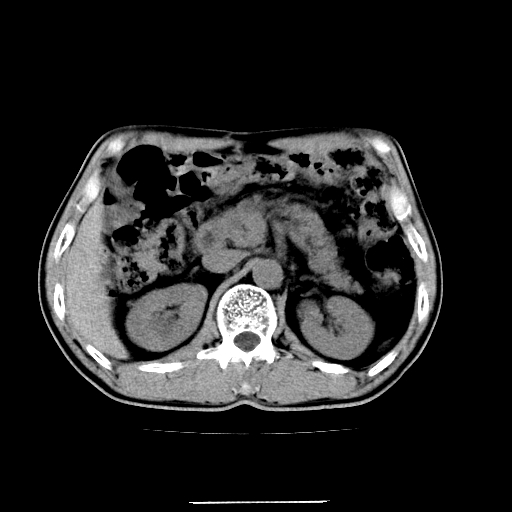

患者男,64岁,胃癌术后三个月,无明显不适。请讨论一下胰头前方小圆形低密度影为淋巴结还是肠管?

应该考虑是肠管,理由1、平扫和增强对比,形态和内部的密度有明显改变。2、增强图片可见明显气液平面。

是肠管影,肠壁有强化。

十二指肠

支持肠管,建议口服5%泛影葡胺5/10分钟扫描